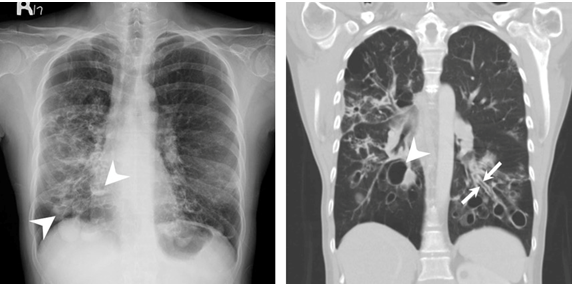

下肺可见增厚的支气管壁相互平行,管径一致,形成典型的双轨征(长箭头)

扩大的支气管伴有相邻的较小的肺动脉分支为印戒征,印戒征是支气管

胸片可见上叶较多轨道征和印戒征;b.